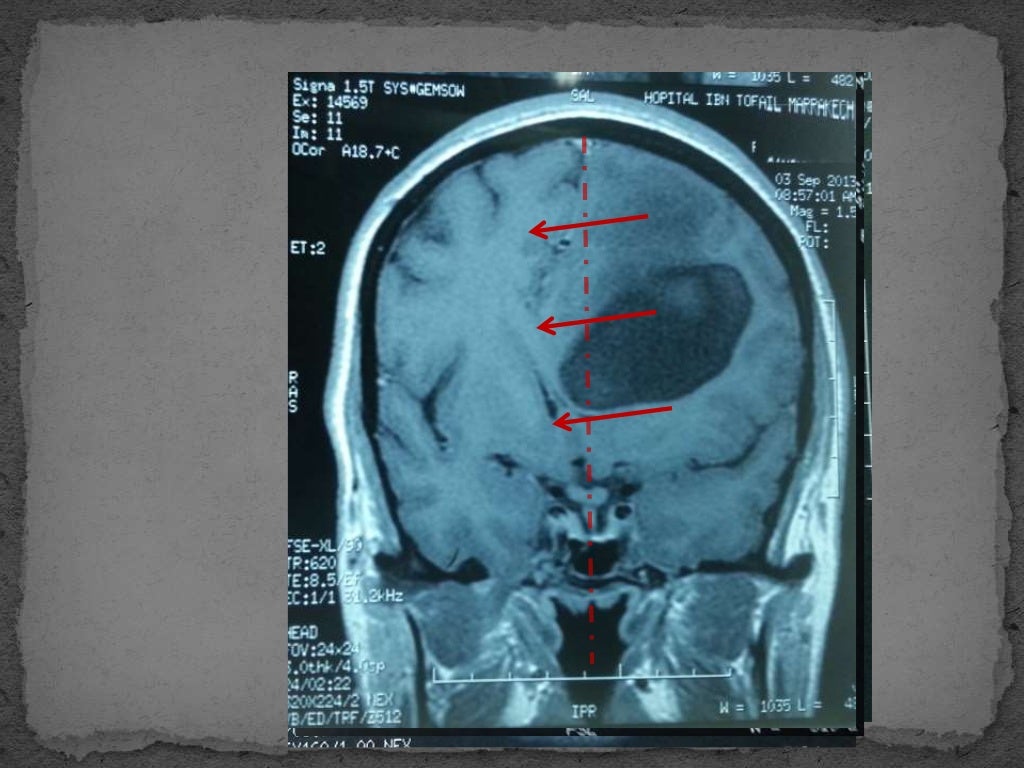

Hypertension intracrânienne

hticQuels sont les signes de l'hypertension intracrânienne ? Quels sont les risques ? Quelle est le traitement ? L'avis du Pr Patrick Mertens, neurochirurgien. • Céphalée, vomissements, papillœdème, parésie VI • AEC (compression SRA), signes engagement.ASPECTS CLINIQUES Les symptômes et signes cliniques des thromboses vei-neuses cérébrales (TVC) sont très variés, et il est néces-saire d’évoquer facilement une TVC pour faire un diagnostic précoce. ALGORITHME PRISE EN CHARGE.e compliquée d’un engagement cérébral, doit être débuté chez tout les patients qui ont des signes et symptômes le suggérant.Decompressive craniectomy in cerebral venous thrombosis: a single centre experience. Les symptômes cliniques les plus courants sont une baisse de la vision, troubles oculaires, vomissements, maux de tête.Étude rétrospective visant à objectiver les signes cliniques et radiologiques d’HTIC chez 116 patients ayant une TVC confirmée à l’angiographie par résonance magnétique. Meningoencéphalocèle. Les TVC peuvent survenir à tout âge, avec un âge moyen de 40 ans, un sex ratio de trois hommespourunefemme.Définition clinique.MMD 6513 – Anesthésie et système nerveux Antoine Halwagi, MD FRCPC Définition HTIC • Imagerie .Signes cliniques Les signes cliniques de l’HTIC relèvent de trois mécanismes : l’HTIC elle-même, les déplacements de structures cérébrales et l’ischémie cérébrale. Atteinte du crâne et de la face; Atteinte respiratoire; Atteinte cardiovasculaire; Atteinte neurologique; Traumatisme du rachis cervical : tout patient ayant un traumatisme crânien grave doit être considéré comme un traumatisé du rachis cervical; 4.

Les formes frustes sont fréquentes (céphalées fluctuantes et peu intenses, sans horaire particulier, sans vomissement . Le terme « idiopathique » est imparfait car il inclut classiquement les formes sans cause évidente et les patients chez lesquels un facteur déclenchant .Évaluation clinique : signes HTIC, troubles de la conscience, signes neurologiques focaux TDM avec et sans injection Méningo-encéphalite (signes cliniques ++) (5) Si IRM négative, en l’absence de CI PL (1) : cellularité normale ou peu élevée, hyperprotéinorachie, examen cytologique TDM ou IRM : lésions temporales ou fronto-temporales .Les symptômes, quand ils existent, sont généralement mineurs. PRINCIPES RÉGISSANT LE TRAITEMENT. L'augmentation de la pression intracrânienne peut être provoquée par les troubles suivants. FonD D’ŒiL L’examen au fond d’œil à la recherche du classique œdème papillaire témoignant d’une HTIC n’est pas satisfaisant, .Diagnostic Signes cliniques d'appel L'hypertension intracrânienne (HTIC) est le signe d'appel le plus fréquent, se manifestant typiquement par des céphalées intenses (classiquement matinales) et des vomissements.L’origine vagale d’un malaise n’est retenue qu’après un interrogatoire circonstanciel, un examen méticuleux et un ECG concordant avec cette hypothèse, car de nombreuses étiologies de mauvais pronostic peuvent se dissimuler derrière un masque vagal. Œdème papillaire de stase par hypertension intracrânienne (HTIC) Clinique : éclipses visuelles à type de flou visuel uni- ou bilatéral, durant quelques secondes, sur venant lors des changements de position; les autres signes d'HTIC sont habituellement associés. Il est indispensable de toujours rechercher des signes d’HTIC afin d’éliminer une situation d’urgence. La HTIC est un trouble grave qui doit être traité immédiatement. Elles surviennent tout d'abord le matin au réveil, puis progressivement s'aggravent, et réveillent le patient durant la nuit, plus précisément la seconde partie de la nuit. PRISE EN CHARGE. Face à une reconstitution . Elargissement du cavum de Meckel.

C’est une urgence neurochirurgicale qui demande une évacuation de L’engagement de l .Les signes cliniques habituels de l’hypertension intracrânienne idiopathique sont les céphalées et les troubles visuels.Définition HTIC • Clinique • Degré de suspicion • Selon pathologie – mécanisme • Selon localisation – zone éloquente, fosse postérieure. Il peut également survenir lors des efforts.HEMATOMES INTRA-PARENCHYMATEUX A. Cette opération permet de réduire la pression exercée .L'engagement cérébral est une complication d'un trouble qui provoque une augmentation de la pression intracrânienne.Quels sont les symptômes de l'hypertension intracrânienne ? Les symptômes de l'HII peuvent varier en fonction de la gravité de la condition, mais les plus courants sont des maux de tête persistants, des problèmes de vision, notamment une vision floue ou double, des acouphènes (souvent pulsatiles), et des nausées ou des vomissements. Ptose des amygdales cérébelleuses.L'hypertension intracrânienne (HIC) est définie par l'existence d'une pression intracrânienne supérieure à 15 mmHg de façon durable.Les symptômes associés aux HPO sont très hétérogènes (douleurs basi-thoraciques, dyspnées, régurgitations, pneumonies à répétitions, anémie ferriprive). Examens et signes cliniques 4.

Symptômes de l’hypertension intracrânienne idiopathique. Ces patients ont une altération de l’état de conscience progressive. Le diagnostic positif repose sur l’IRM encéphalique et orbitaire qui élimine le diagnostic de processus expansif intracrânien et de thrombophlébite cérébrale et montre des signes spécifiques au niveau orbitaire. Le syndrome méningé regroupe : Céphalée : quasi-constante, irradie ++ vers la nuque et la colonne, très évocatrice lorsqu'elle est associée à des rachialgies et/ ou est majorée au bruit (sonophobie), à la lumière (photophobie) ou au contact cutané; Contractures musculaires : raideur de nuque quasi-constante, signe de Brudzinski (= .Activité : Journaliste Scientifique

#8 item 299 : Hypertension intracrânienne

Des signes d'HTIC (céphalées à prédominance matinale ou en seconde partie de nuit avec réveils nocturnes, exagérées par l'effort ou la position couchée, résistant aux antalgiques, accompagnées de vomissements matinaux pouvant les soulager temporairement) sont en général présents mais leur absence ne permet pas d'écarter cette hypothèse.